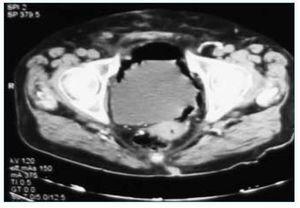

Durante el seguimiento, y a raíz de un dolor abdominal inespecífico localizado en área hipogástrica en el segundo mes tras el trasplante, se realizó una tomografía axial computerizada (TAC), en la que se observó una colección de aire en la pared interna de la vejiga1, sin observarse en ese momento anomalías en el injerto (fig. 1). La paciente estaba totalmente asintomática, a excepción de una infección urinaria causada por E. Coli, que fue tratada con ertapenem durante dos semanas. Veinte días más tarde se realizó una nueva TAC, en la que la vejiga aparecía completamente normal, desapareciendo por completo la colección de aire. Durante más de dos semanas la paciente fue portadora de una sonda uretral, que se retiró tras la normalización de la imagen radiológica.

Figura 1.